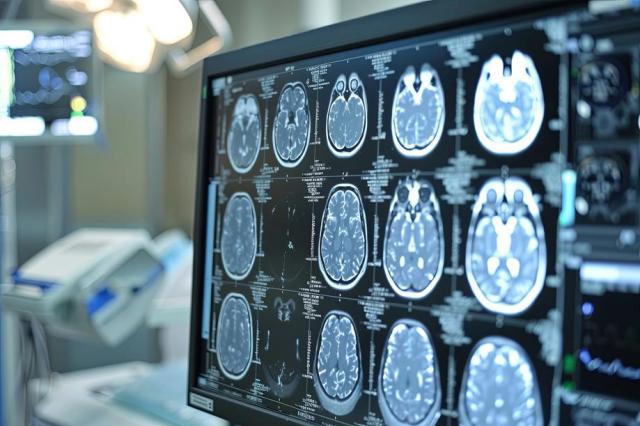

Palermo, 16 dic. (Adnkronos) - Portare dalla carta alla pratica il Piano nazionale malattie rare (PNMR) 2023–2026 nel campo delle encefalopatie dello sviluppo ed epilettiche (DEEs), trasformando indirizzi normativi e decreti regionali in percorsi assistenziali realmente operativi. È questo il messaggio chiave emerso dal convegno 'DEEstrategy e Rete delle malattie rare in Sicilia: continuità assistenziale e transizione dall’età pediatrica all’età adulta', organizzato da Sineos Healthcare Solutions, con la sponsorizzazione non condizionante di UCB, che si è svolto oggi all'Ars sotto l’egida del direttore Dipartimento interaziendale Farmaceutico Asp Palermo Maurizio Pastorello e di Maria Piccione, referente coordinamento MR Regione Sicilia, direttore Uoc genetica medica Azienda ospedali riuniti Villa Sofia-Cervello Palermo. Un appuntamento di rilievo istituzionale e sanitario che ha segnato un passaggio decisivo per la governance delle malattie rare in Sicilia, ponendo l’accento sulla necessità di rendere esecutivo il decreto assessoriale del 27 maggio 2025 dedicato al riordino della Rete regionale delle malattie rare.

Lo Spoke viene così riconosciuto non come struttura “accessoria”, ma come elemento strategico del sistema, capace di trasformare la rete da concetto teorico a infrastruttura clinica funzionante. “Le malattie rare rappresentano una sfida clinica in continua evoluzione - ha sottolineato Maria Paola Campisi, dirigente medico Uoc Cardiologia P.O. Ingrassia Asp Palermo - Si tratta di un gruppo eterogeneo di patologie che, se non correttamente inquadrate e gestite, hanno un impatto significativo sulla morbilità e mortalità. Da qui l’importanza di creare una rete attraverso il ruolo dei centri Hub e Spoke sul territorio siciliano per garantire un accesso equo e tempestivo a tutti gli strumenti diagnostici avanzati (RMN, Medicina Nucleare, Genetica). Strategie concrete per la Sinergia tra Ospedale-territorio e la sostenibilità farmacologica per dare beneficio a tutti i nostri pazienti che convivono con queste patologie ancora oggi sotto diagnosticate”.